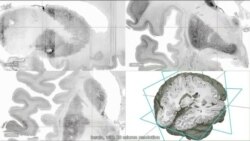

The project is called BigBrain. In three dimensions and intricate detail, it reveals the anatomy of the brain as never seen before.

“These are images of a 3-D reconstructed human brain with a spatial resolution of 0.02 millimeters. So this is even thinner than a thin human hair, and it allows [us] to see the microstructure of the human brain in 3-D space,” said Katrin Amunts, director of the Vogt Institute for Brain Research at Germany's Heinrich Heine University, a partner in the project.

To create it, the researchers first cut the brain into 7,400 slices, each 20 micrometers thick, then stained each slice with a special dye so all the cell bodies were visible. After that, the slices were digitized and carefully realigned.

“This involved us in both manual activity in shifting broken pieces of the data into the right spatial location and then a large amount of computational analysis," said Alan Evans at McGill University, who was in charge of digital reconstruction, "which allowed us to overcome the distortions, both the geometric and optical, to reassemble the data into a coherent three-dimensional form.”

The resolution on the reference brain is 50 times greater than the standard brain scans currently available. Its images allow scientists to better visualize what’s happening in certain areas of the brain. BigBrain paves the way to understanding how the brain’s anatomy contributes to language, learning and other processes, or how its shape relates to chemical signaling or gene expression.